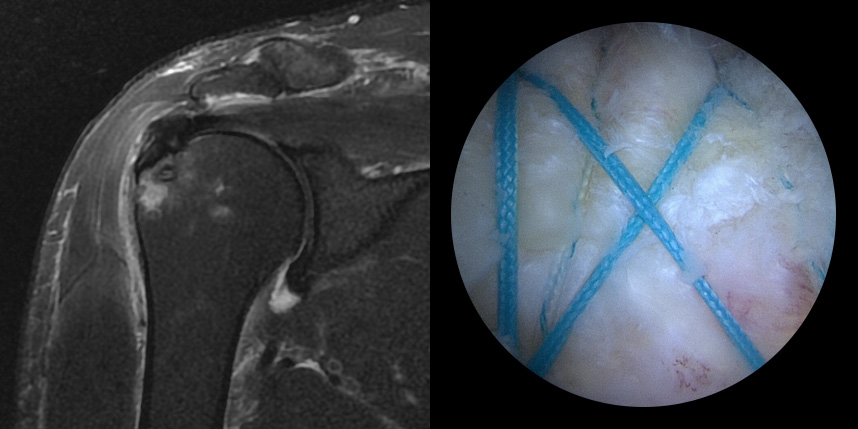

완전 파열시

브릿지 봉합술

접촉면접과 힘줄

부착 압력이 높습니다.

초기,중기,말기 파열에

주로 사용됩니다.

상대적으로

재파열율이 낮습니다.